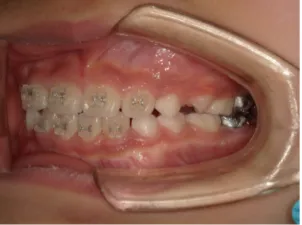

治療中④小2(8y2m)~小3(9y1m):QHとBHで拡大・アーチ形態の修正、ブラケットで前歯の並べ替えまで終了

治療中⑤小3(9y2m):モノブロック装置(筋機能的咬合誘導装置)で永久歯の咬み合わせ治療へ移行

| 行ったご提案・診断内容 | 成長期に行う治療と咬合治療をご提案 受け口用ファンクショナルアプライアンス(写真②③)からスタートし、小2以降で上下顎の拡大・歯列弓の形態修正・前歯の並べ直し(写真④)を行いその後、モノブロック(筋機能的咬合誘導)装置(写真⑤)へ移行し、受け口の再発予防と永久歯を適切な咬み合わせに誘導し、必要によりマルチブラケット法へ移行する治療方法を提案しました。 成長期治療(成長時期にお口の環境を整える治療) 2年生以降から 咬合治療 |